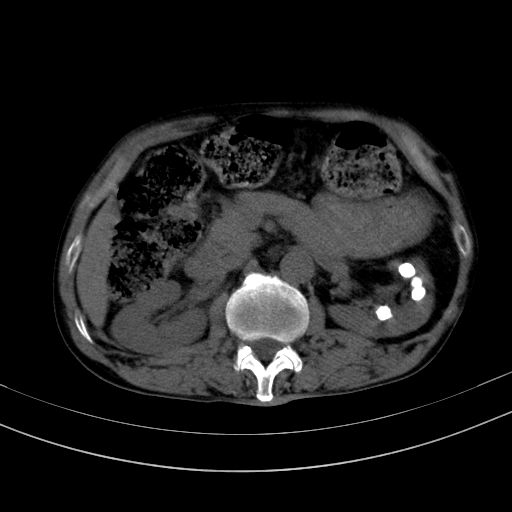

以下是引用37度在2010-1-9 14:37:00的发言:[br]1.双肾囊肿,左肾积水结石,.胆总管轻度扩张;[br]2.病灶在腹膜外,考虑纤维瘤。

以下是引用dyqct在2010-1-9 17:56:00的发言:[br]考虑:1.双肾囊肿,左肾积水结石、旋转不良。[br] 2.右侧腹直肌血肿或纤维瘤。[br]肠道准备不好。做个增强。